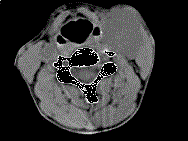

问题 女,39岁,左颈部可扪及一肿块,无发热,无疼痛,CT如图所示,最可能的诊断是 ( )

选项 A、颈部海绵状血管瘤 B、颈动脉瘤 C、颈动脉体瘤 D、颈部神经纤维瘤 E、颈部神经鞘瘤

答案 C